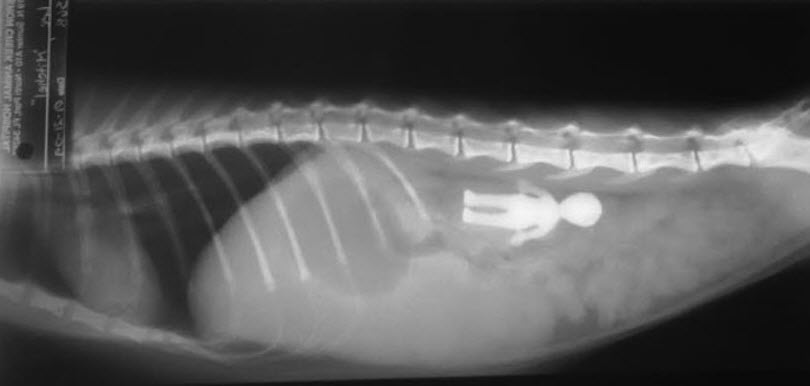

They ate what